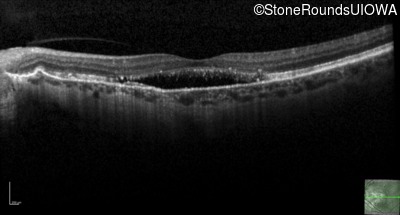

Age at visit: 58 years